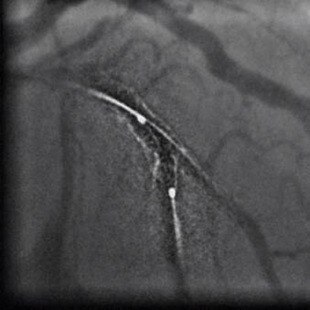

1. La solution PCI ASSIST comprend StentViz et StentVesselViz, qui sont des fonctions des systèmes de radiographie interventionnelle Innova IGS 5, Innova IGS 6, Discovery IGS 7 et Discovery IGS 7 OR.

3. Amélioration par rapport au même test sans l'option PCI ASSIST. L'amélioration de la visibilité et de la QI est mesurée sur Innova IGS 530 grâce à des fantômes utilisant différentes épaisseurs de plexiglas, des paramètres d'acquisition et la roue à rayons NEMA (réf 1), qui calcule le rapport du contraste des câbles mobiles et du niveau de bruit de fond. Le niveau d'amélioration de la qualité d'image lié à PCI ASSIST dépend des paramètres d'acquisitions, de la procédure clinique réalisée, de la taille du patient, des mouvements de l'image, de l'emplacement de la structure anatomique et des méthodes employées par l'établissement. Réf 1 : A new tool for benchmarking cardiovascular fluoroscopes; S. Balter, Radiation Protection Dosimetry, Vol. 94, No. 1-2 pp. 161-166 (2001). Applicable aux systèmes Innova IGS 5 (configurations IGS 520, IGS 530), Innova IGS 6 et Discovery IGS 7 (configuration IGS 730).